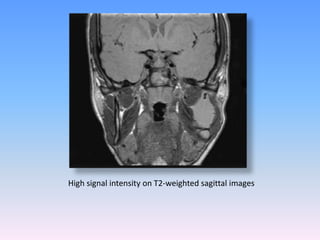

MRI:

The MRI finding of KCOTs is described as uniformly thin walls

with weak enhancement and fluids of heterogenous signal

intensity.

The contents of the cysts frequently showed intermediate or

high T1- weighted signal intensity or intermediate T2-weighted

signal intensity.

In multilocular and large lesions

T-1 weighted MR image showed the lesion with thick, strongly

enhanced walls of uniform thickness

And heterogeneous fluid contents in T-2 weighted MR image.

MR images demonstrate the low signal intensity on

T1-weighted axial (a) and sagittal (b) images

Nurhan G¨uler etal ConservativeManagement of Keratocystic Odontogenic Tumors of Jaws ; 2011

High signal intensity on T2-weighted sagittal images